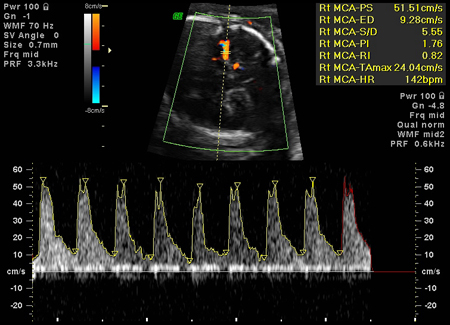

Aumento de la velocidad en la arteria cerebral media, coherente con anemia fetal grave

Ottawa Hospital; utilizado con el consentimiento de la paciente